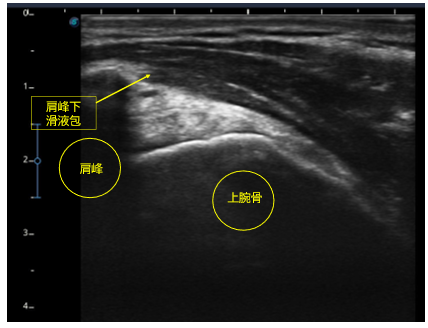

[エコー問題の解答例]

※超音波エコー評価とアプローチの選択 運動器リハに必須のエコー測定とアプローチ 上肢編では、プローブの当て方や画像の描出方法について詳しく解説します。

※画像は筆者が作成